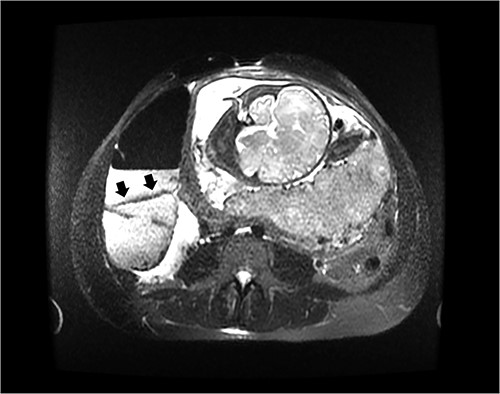

On hospital day 2, the patient became obstipated, and her abdominal exam had notable distension with persistent right upper quadrant tenderness. An abdominal magnetic resonance imaging (MRI) was performed revealing dilated small intestine with air-fluid levels and an inverted-appearing, prominent cecum (Figs. 1 and 2). The patient was diagnosed with an acute abdomen from probable cecal volvulus versus appendicitis and was urgently taken to the operating room for cesarean section (c-section) to facilitate abdominal exploration. After delivery of the child, a cecal bascule was found, with a severely distended cecum (Fig. 3). Because the cecum and ascending colon were deserosalized, a right hemicolectomy with primary ileocolic anastomosis was performed. The patient had return of bowel function on post operative day 5 and was discharged home on day 7.

Axial image of an abdominal MRI on a 36-week pregnant patient with a dilated cecum anteriorly displaced to the ascending colon. Arrows mark the point of inflection.

Another cause for the delay in diagnosis is the clinician’s hesitancy to order diagnostic radiologic imaging in pregnant patients due to the fear of harm to the fetus [22, 23]. The opinion of the American College of Obstetricians and Gynecologists is that the radiation exposure of plain X-ray, CT or nuclear medicine technology is at a dose much lower than the exposure associated with fetal harm and that the maternal benefit from early and accurate diagnosis of acute processes such as appendicitis or bowel obstruction outweighs the theoretical fetal risks [24]. Yet, US and MRI are not associated with fetal risk and should therefore be considered first when available. The utility of US for diagnosing a cecal bascule or other bowel obstruction is poor as evidenced by the normal US in the case reports by Lazarus and ours [9]. However, US is still recommended in the pregnant patient with abdominal pain because of its safety and ability to diagnose obstetric or gynecologic etiologies for pain [9]. A cecal bascule on plain abdominal X-ray is characterized by distension of the cecum, paucity of gas in the distal colon, dilated small bowel and gas shadow within the pelvis [3]. CT scan shows displacement of the cecum to the upper or central abdomen, the ileocecal valve to the right upper quadrant and a transition zone between cecum and ascending colon [3]. The sensitivity of diagnosing a cecal bascule in a nonpregnant patient by CT scan is 61% [3]. Diagnosis of cecal bascule by MRI was not found in literature. The MRI for our patient showed an anterior and superior inversion of the cecum.